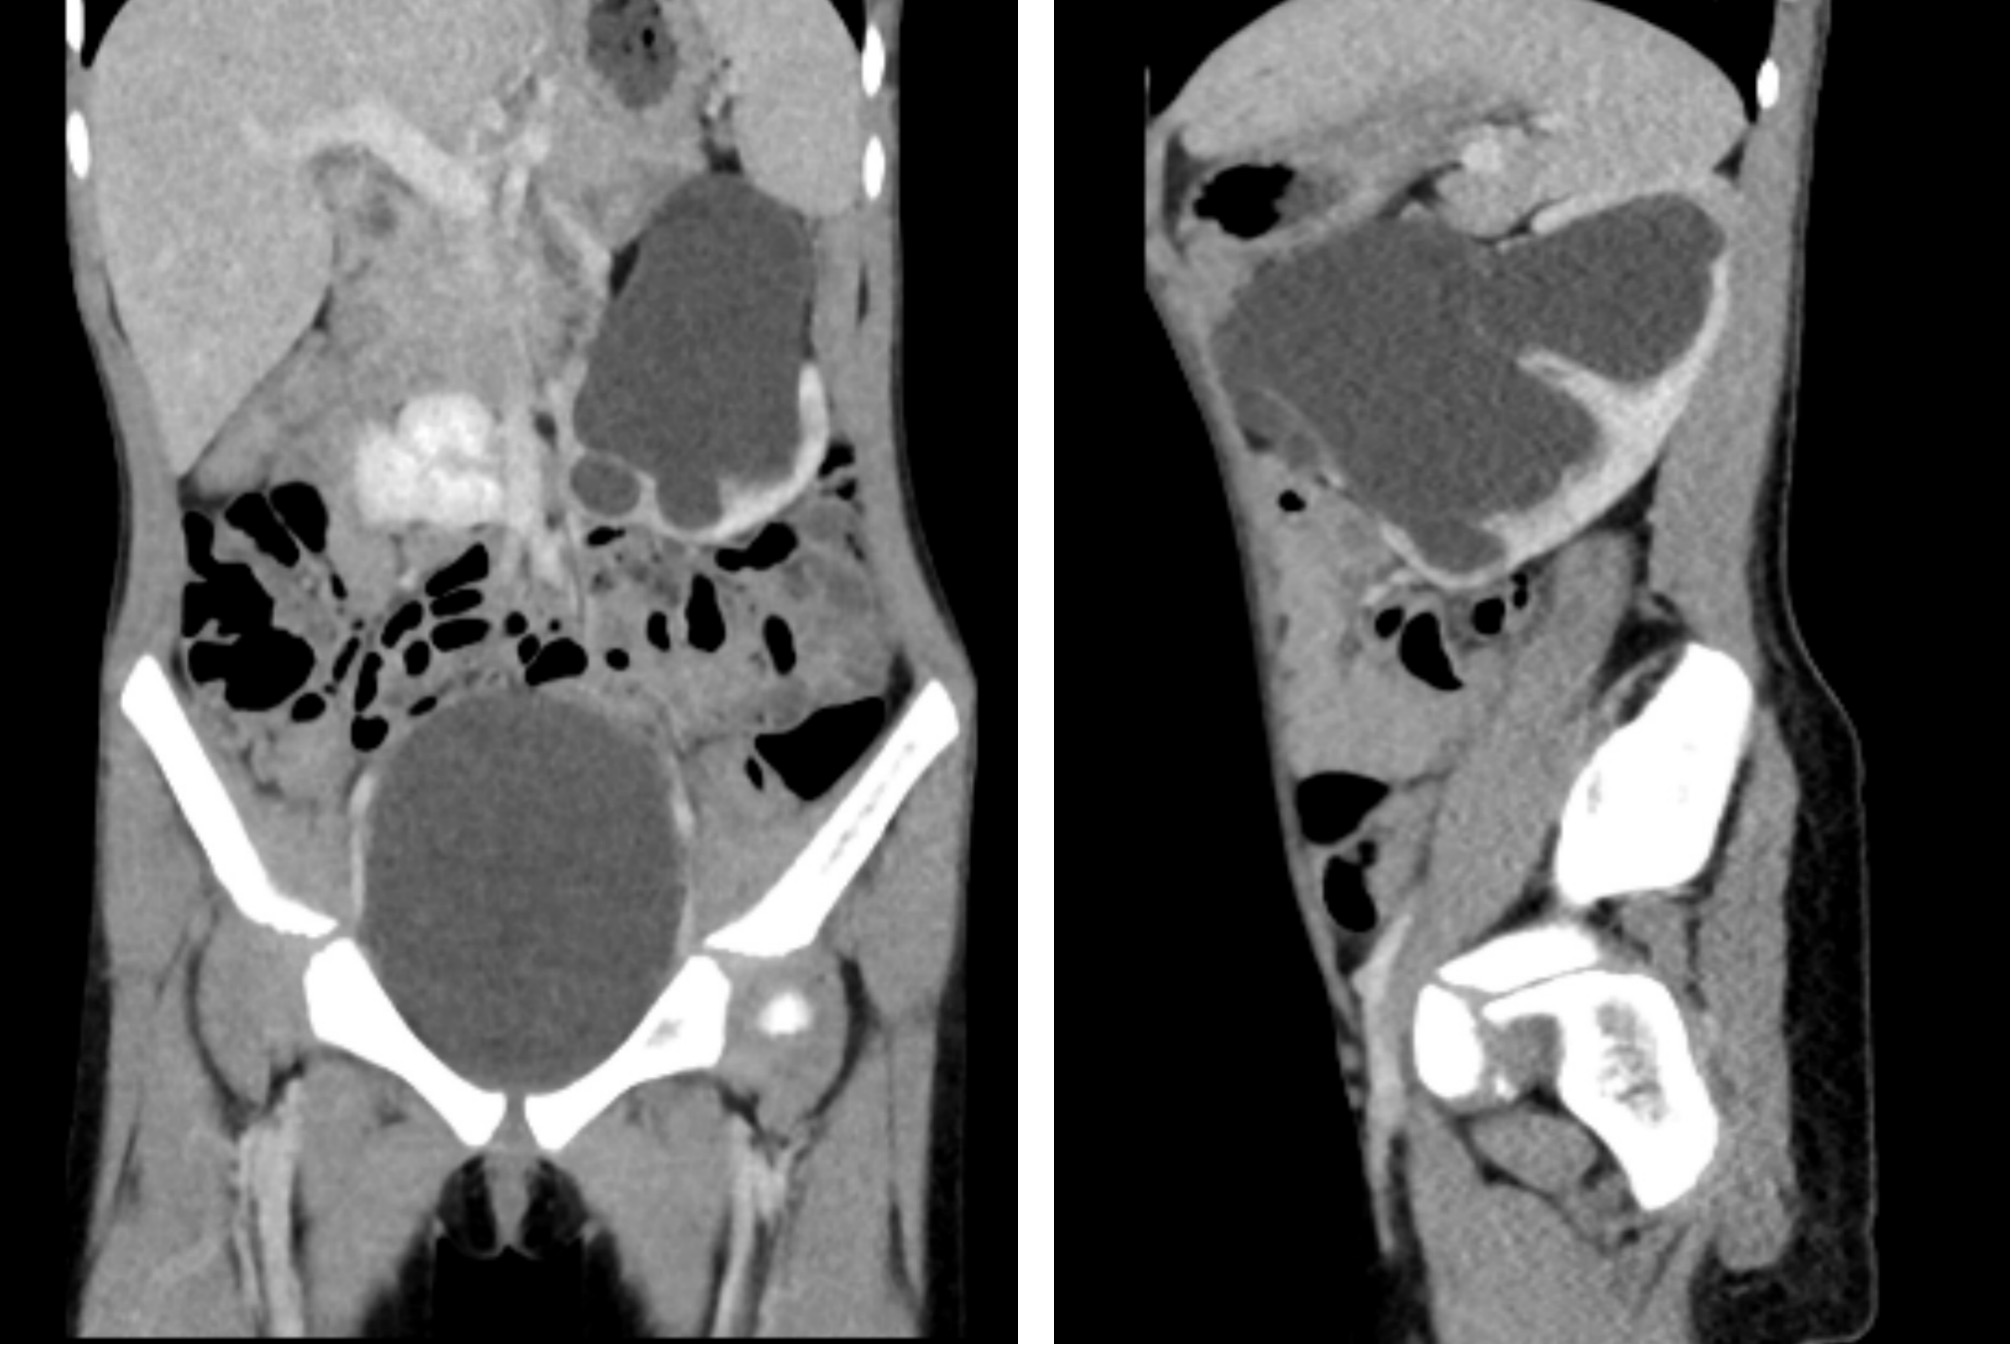

据了解,患儿依依(化名)多月来反复出现不明原因的腹痛及呕吐,经仔细检查后,被确诊为先天性马蹄肾——一种因两侧肾脏在下极融合导致的罕见结构异常,常伴随肾脏旋转不良及血管变异。该多发畸形已造成其左侧肾脏严重积水,若不及时干预,将进一步损害患儿依依的肾功能,甚至需切除肾脏。

面对这一复杂病情,医院启动了多学科协作机制,由小儿外科和泌尿外科团队共同研究影像资料,结合患儿具体情况,为其制定了个性化的微创手术方案。

手术中,在麻醉科团队的配合下,运用达芬奇机器人手术系统成功离断马蹄肾峡部,解除异位血管对输尿管的压迫,纠正了旋转不良的左肾,从而有效解除梗阻,最大限度保留肾功能。手术过程顺利,出血量少,患儿术后恢复良好。最新超声复查结果显示,依依的肾积水已明显减轻,其腹痛症状完全消失,目前已恢复正常学习和生活。